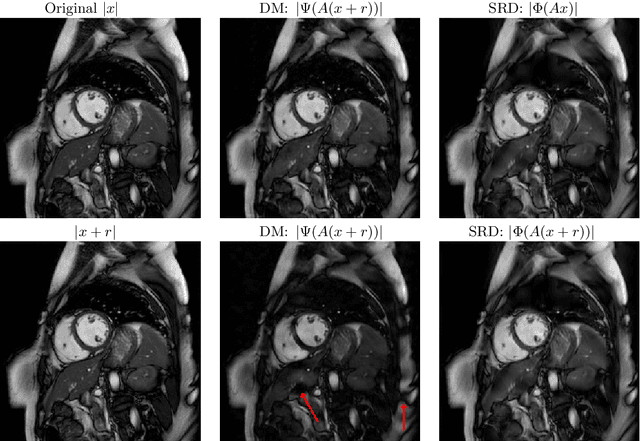

Abstract:There is overwhelming empirical evidence that Deep Learning (DL) leads to unstable methods in applications ranging from image classification and computer vision to voice recognition and automated diagnosis in medicine. Recently, a similar instability phenomenon has been discovered when DL is used to solve certain problems in computational science, namely, inverse problems in imaging. In this paper we present a comprehensive mathematical analysis explaining the many facets of the instability phenomenon in DL for inverse problems. Our main results not only explain why this phenomenon occurs, they also shed light as to why finding a cure for instabilities is so difficult in practice. Additionally, these theorems show that instabilities are typically not rare events - rather, they can occur even when the measurements are subject to completely random noise - and consequently how easy it can be to destablise certain trained neural networks. We also examine the delicate balance between reconstruction performance and stability, and in particular, how DL methods may outperform state-of-the-art sparse regularization methods, but at the cost of instability. Finally, we demonstrate a counterintuitive phenomenon: training a neural network may generically not yield an optimal reconstruction method for an inverse problem.

Abstract:Deep learning, due to its unprecedented success in tasks such as image classification, has emerged as a new tool in image reconstruction with potential to change the field. In this paper we demonstrate a crucial phenomenon: deep learning typically yields unstablemethods for image reconstruction. The instabilities usually occur in several forms: (1) tiny, almost undetectable perturbations, both in the image and sampling domain, may result in severe artefacts in the reconstruction, (2) a small structural change, for example a tumour, may not be captured in the reconstructed image and (3) (a counterintuitive type of instability) more samples may yield poorer performance. Our new stability test with algorithms and easy to use software detects the instability phenomena. The test is aimed at researchers to test their networks for instabilities and for government agencies, such as the Food and Drug Administration (FDA), to secure safe use of deep learning methods.